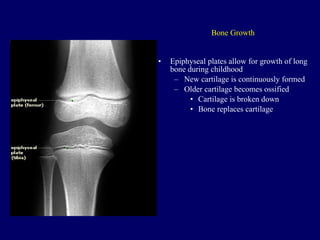

Bone Growth Epiphyseal plates allow for growth of long bone during childhood New cartilage is continuously formed Older cartilage becomes ossified Cartilage is broken down Bone replaces cartilage

Gross Anatomy ofa Long Bone Epiphyseal line Thin line of bony tissue spanning the epiphysis that looks different from the rest. Is the remnant of the epiphyseal plate. (growth) The epiphyseal plate (hyaline cartilage) is seen in young, growing bone. Figure 5.2a

Bone Growth Epiphysealplates allow for growth of long bone during childhood New cartilage is continuously formed Older cartilage becomes ossified Cartilage is broken down Bone replaces cartilage